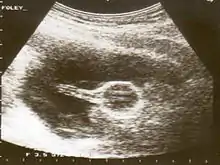

Cervical

A Foley catheter can also be used to ripen the cervix during induction of labor. When used for this purpose, the procedure is called extra-amniotic saline infusion.[6] In this procedure, the balloon is inserted behind the cervical wall and inflated, for example with 30-80 mL of saline.[6] The remaining length of the catheter is pulled slightly taut and taped to the inside of the woman's leg. The inflated balloon applies pressure to the cervix as the baby's head would prior to labor, causing it to dilate. As the cervix dilates over time, the catheter is readjusted to again be slightly taut and retaped to maintain pressure. When the cervix has dilated sufficiently, the catheter drops out.[7]